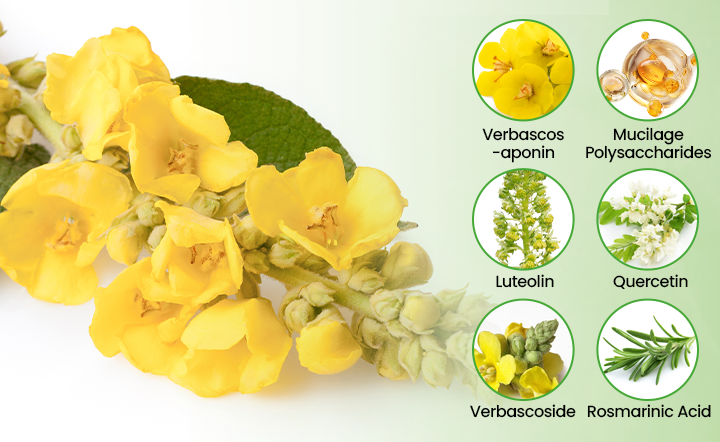

Advanced Mullein Extract: 50:1 Concentration Technology

Not all mullein extracts are created equal. Qooes® Breatheora uses pharmaceutical-grade 50:1 concentration technology - meaning 50 pounds of raw mullein leaves are concentrated into every 1 pound of extract. Most commercial mullein products contain 4:1 or weaker extracts with minimal active compounds.

Active Compound Analysis (Per Gram Extract) :

Verbascosaponin (Primary Expectorant): 12.5mg - facilitates natural mucus clearance Mucilage Polysaccharides (Demulcent): 8.7mg - soothes irritated tissues Luteolin & Quercetin (Anti-inflammatory): 6.2mg - reduces respiratory inflammation Verbascoside (Antimicrobial): 4.1mg - supports healthy respiratory environment Rosmarinic Acid (Antioxidant): 3.8mg - protects against environmental damage

Pharmaceutical-Grade Processing: Our extraction facility uses CO2 supercritical extraction technology - the same method used for high-end pharmaceuticals - ensuring maximum potency and purity without harmful solvents.